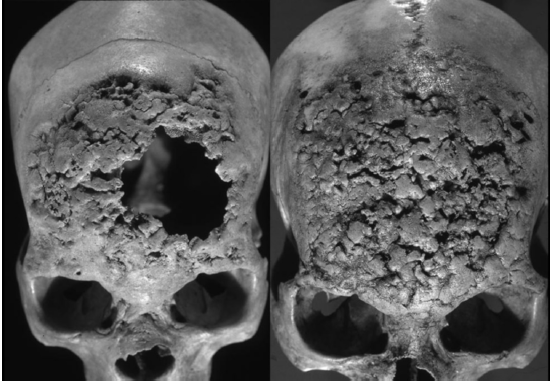

La evidencia bioarqueológica de treponematosis hallada en contextos prehispánicos y coloniales de México ha sido extensamente documentada e investigada [Mansilla et al. 1995, 2005; Márquez et al. 2015; Molto 2005; Salas 1982]. Mansilla y Pijoan [2005] analizaron las colecciones esqueletales de nueve sitios arqueológicos de varios estados de México datando del 900 a. C. hasta el 1520 d. C.. Este estudio demostró la presencia de treponematosis en el México prehispánico y encontró que las presentes enfermedades incrementaron en frecuencia a partir del 1000 d. C. Algunos de los ejemplos más notables de enfermedades treponémicas fueron encontrados en individuos excavados en la cueva de la Candelaria en Coahuila (1100-1300 d. C.) [Pineda et al. 2009]. En este sitio se recuperaron 116 cráneos, de los cuáles 60 presentaban lesiones líticas con formación de hueso reactivo en la bóveda craneal. Además, dos de los 60 cráneos también presentaban caries sicca, una lesión patognomónica de la infección treponémica [Pineda et al. 2009] (figura 3).

Fuente: Pineda y colaboradores 2009 e inah-daf.

Figura 3. Caries sicca en dos cráneos humanos recuperados de la Cueva de la Candelaria.